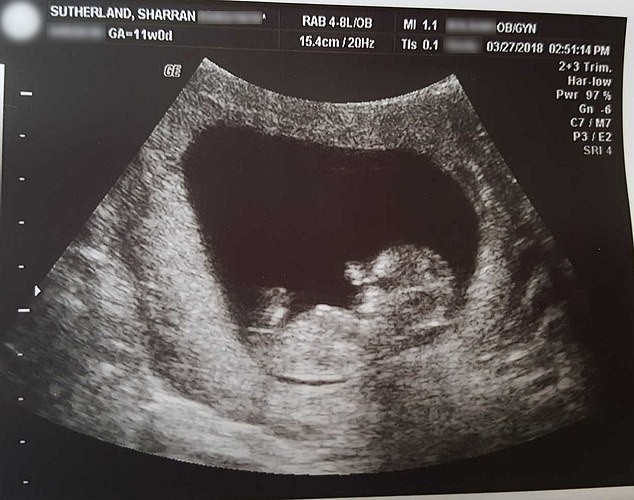

03/11/2018 02:25Đăng ảnh thai nhi 14 tuần bị sẩy đủ hình hài, người mẹ kêu gọi phụ nữ ngừng phá thai vì quá tội lỗi

Thai nhi 14 tuần tuổi đã là "một em bé thực sự"

Bà mẹ đó là Chritian Sharran Sutherland (40 tuổi, hiện đang sinh sống ở bang Missouri, Mỹ). Sharran bị sảy thai và mất đi đứa con mới chỉ 14 tuần tuổi trong bụng mẹ. Cô quyết định chia sẻ hình ảnh thai nhi với bàn tay, bàn chân nhỏ xíu, vô cùng xinh xắn để mọi người biết rằng, em bé đã "thành hình một cách trọn vẹn" dù mới chỉ được 14 tuần tuổi. Thời điểm này, cơ thể con trai cô chỉ dài hơn 10cm và cân nặng 22,6g.

Bác sĩ của Sharran thúc giục cô thực hiện thủ thuật nong và nạo tử cung (D&C) để đưa thai nhi ra khỏi cơ thể cô sau khi siêu âm phát hiện tim bé không còn đập nữa. Nhưng Sharran từ chối bởi cô "không muốn con mình chào đời trong vụn vỡ". Thay vào đó, cô quyết định nhờ tới biện pháp kích đẻ và sinh thường vào ngày 23/4 – 173 ngày trước ngày dự sinh của bé.